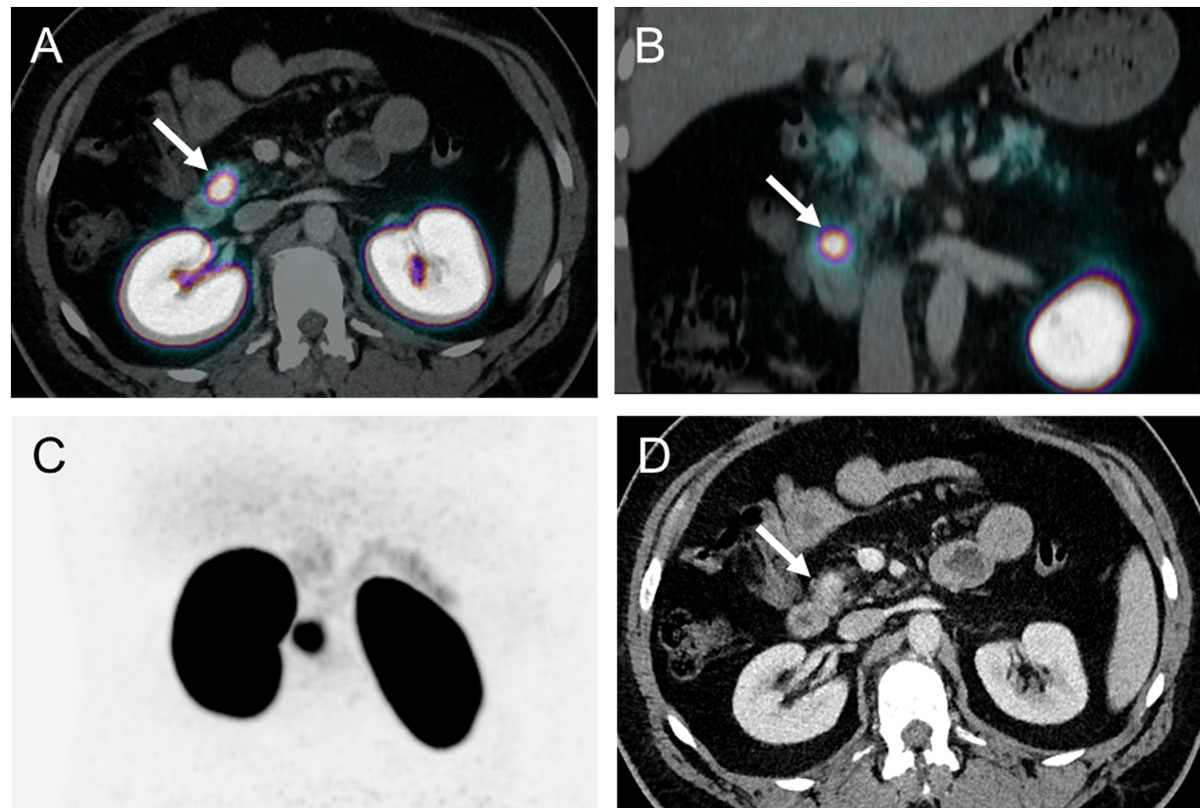

Based on these promising data, a prospective study including 52 consecutive patients was conducted at the University Hospital of Basel. The aim was to compare the diagnostic accuracy and clinical impact of 68Ga-DOTA-exendin-4 PET/CT in comparison with 111In-DOTA-exendin-4 SPECT/CT and 3-Tesla-MRI. The data from this study showed the superiority of 68Ga-DOTA-exendin-4 PET/CT (fig. 4) in comparison with 111In-DOTA-exendin-4 SPECT/CT and 3-Tesla-MRI [37].

Figure 4 GLP-1 receptor targeting using 68Ga-DOTA-exendin-4. Patient with endogenous hyperinsulinaemic hypoglycaemia without evidence of an insulinoma in the prior external scans.

Transaxial (a), coronar (b) and MIP (c) of PET/CT 2.5 h after injection of 68Ga-DOTA-exendin-4 and transaxial contrast enhanced CT (d). PET/CT (b) shows a clear focal uptake in the head of the pancreas and histological evaluation confirmed a benign insulinoma. Contrast enhanced CT shows only a discrete diffuse contrast enhancement in the head of the pancreas.